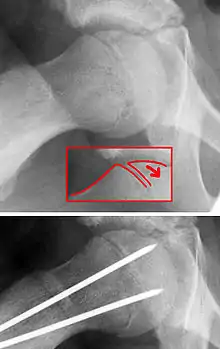

| X-ray showing a slipped capital femoral epiphysis, before and after surgical fixation. | |

The diagnosis requires x-rays of the pelvis, with anteriorposterior (AP) and frog-leg lateral views.[11] The appearance of the head of the femur in relation to the shaft likens that of a "melting ice cream cone", visible with Klein's line. The severity of the disease can be measured using the Southwick angle.

The disease can be treated with external in-situ pinning or open reduction and pinning. Consultation with an orthopaedic surgeon is necessary to repair this problem. Pinning the unaffected side prophylactically is not recommended for most patients, but may be appropriate if a second SCFE is very likely.[11]

Once SCFE is suspected, the patient should be non-weight bearing and remain on strict bed rest. In severe cases, after enough rest the patient may require physical therapy to regain strength and movement back to the leg. A SCFE is an orthopaedic emergency, as further slippage may result in occlusion of the blood supply and avascular necrosis (risk of 25 percent). Almost all cases require surgery, which usually involves the placement of one or two pins into the femoral head to prevent further slippage.[12] The recommended screw placement is in the center of the epiphysis and perpendicular to the physis.[13] Chances of a slippage occurring in the other hip are 20 percent within 18 months of diagnosis of the first slippage and consequently the opposite unaffected femur may also require pinning.